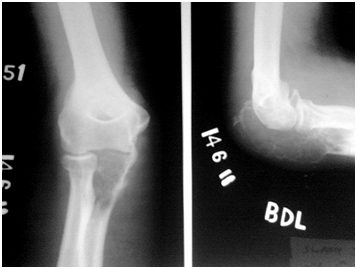

A 30 year old male presented with painless swelling around his right elbow for a period of 4 months (Figure 1). It was insidious in onset with gradual increase in size which later on started to affect his elbow movements. On examination a localised swelling measuring 5x 6cm in posterior aspect of elbow was seen which was non tender, hard in consistency and was continuous with proximal ulna. The overlying skin was normal. Terminal part of extension and flexion of elbow joint was limited. X-ray showed a lytic lesion involving entire proximal ulna with soap bubble appearance with destruction of articular surface (Figure 2). FNAC was done to aid the diagnosis and it showed features suggestive of osteoclastoma.

Figure 2 X-ray at the time of presentation.